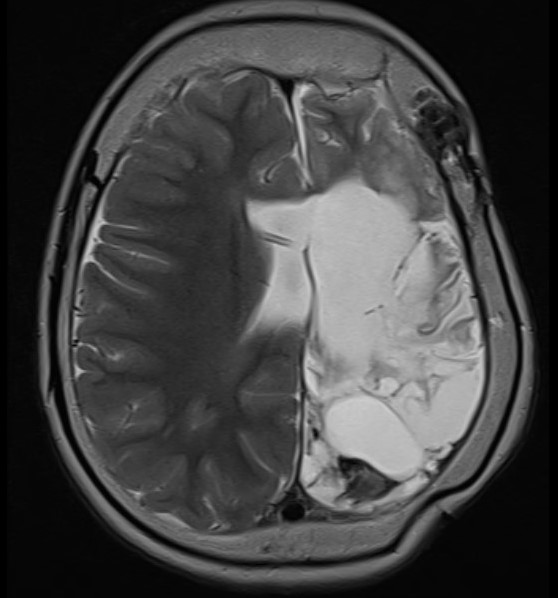

The following images accompany comments at the foot of this post.